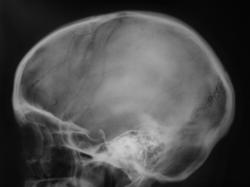

Как следует расценить "тень" на фоне клиновидной (основной) пазухи.

Наверное, сфеноидит. Похоже, что клиновидная пазуха разделена сагиттальной костной перегородкой на две неравные части. Пневматизация бОльшей правой половины не нарушена. А левой - снижена. Вероятно, эта левая часть пазухи и дает неравномерное снижение пневматизации на боковой рентгенограмме. В любом случае, если у пациента головные боли, то вероятность сфеноидита ещё выше (неврологи, кстати, не всегда вспоминают про сфеноидит, когда пользуют пациентов с головной болью). А чтобы сфеноидит доказать без КТ, надо снять околоносовые пазухи с открытым ртом (извините за банальные рекомендации).